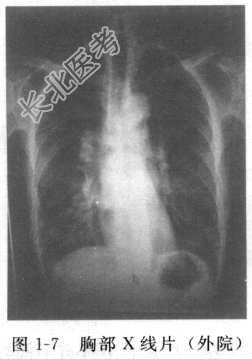

- [材料题] 患者男性,32岁,因“反复发热伴咳嗽、咳痰1周”入院。入院前外院急诊血常规提示WBC 13.6×109/L,N% 78%。胸部X线片(图1-7)示右下肺斑片状影。查体:双肺呼吸音粗,右下肺可闻及湿啰音。外院给予“头孢替安”等抗感染、退热等治疗后体温稍有下降,仍有反复咳嗽、咳痰。